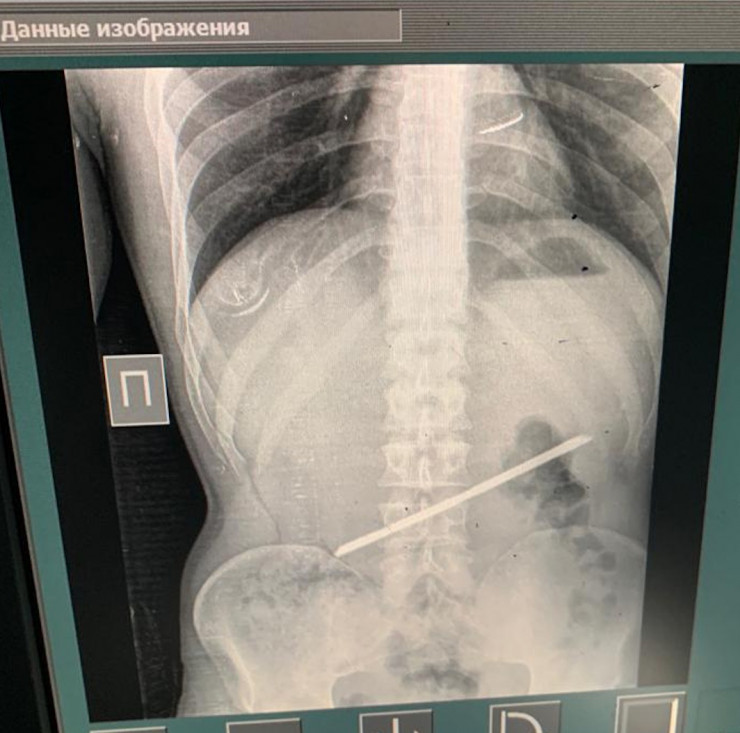

Хирурги в Алматы извлекли 25-сантиметровую арматуру из желудка мужчины, передает Tengrinews.kz со ссылкой на пресс-службу Управления общественного здоровья Алматы.

"28 сентября он сам пришел в больницу с жалобами на острые боли в эпигастральной области. Со слов пациента, более двух лет назад он находился в следственном изоляторе, где и проглотил арматуру. Слова пациента подтвердились в результате рентген-диагностики, мужчину сразу взяли на операцию, проведены: лапаротомия, гастротомия, удаление инородного тела. Операция прошла успешно, пациент переведен в палату пробуждения", - рассказал хирург приемного отделения Городской клинической больницы № 4 Темирхан Кожахметов.

Уникальным врачи называли тот факт, что более двух лет металлический предмет в желудке не доставлял проблем.

"Инородное тело не мигрировало и не повредило стенки желудка. Перфорация и пролежни - самые распространенные из осложнений при подобных случаях. Перфорация - это прорыв инородного тела в свободную брюшную полость с поступлением в нее желудочно-дуоденального содержимого", - сообщили в УОЗ Алматы и предоставили список операционной бригады.